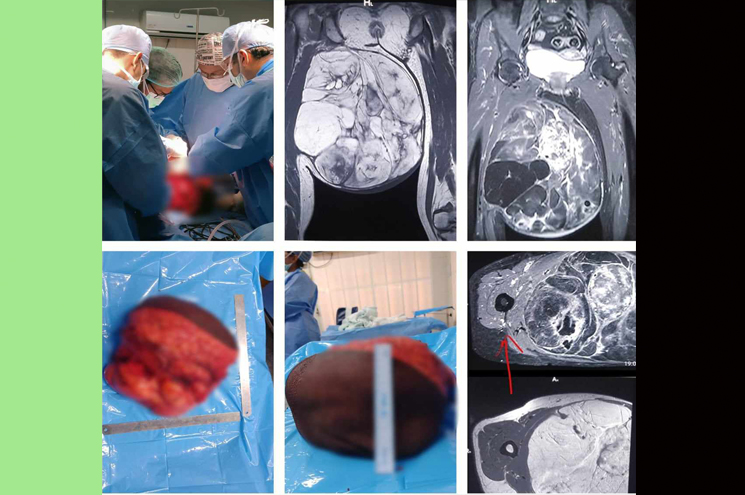

തൃശൂർ: ആറ് മണിക്കൂർ നീണ്ട ശസ്ത്രക്രിയയിലൂടെ 61കാരിയുടെ കാലിന്റെ തുടയോട് ചേർന്ന് വളർന്ന 10 കിലോ ഭാരമുള്ള മുഴ നീക്കം ചെയ്ത് തൃശൂർ മെഡിക്കൽ കോളജ്. തൃശൂര് പുഴക്കല് സ്വദേശിനിക്കാണ് ശസ്ത്രക്രിയ നടത്തിയത്. രോഗിക്ക് ഹെപ്പറ്റെറ്റിസ് രോഗം കൂടി ഉണ്ടായിരുന്നത് ശസ്ത്രക്രിയയുടെ സങ്കീര്ണത വര്ധിപ്പിച്ചിരുന്നു. ശസ്ത്രക്രിയ വിജയമായതോടെ സാധാരണ പോലെ നടക്കാൻ രോഗിക്ക് ഇപ്പോൾ കഴിയുന്നുണ്ട്.

മെഡിക്കല് കോളജിലെ സര്ജറി വിഭാഗവും ഓങ്കോ സര്ജറി വിഭാഗവും ചേര്ന്നാണ് ശസ്ത്രക്രിയ നടത്തിയത്. ശസ്ത്രക്രിയയ്ക്ക് നേതൃത്വം നല്കിയ മുഴുവന് ടീമിനേയും ആരോഗ്യ വകുപ്പ് മന്ത്രി വീണാ ജോര്ജ് അഭിനന്ദിച്ചു. ഒരു മാസം മുമ്പാണ് നടക്കാന് പോലും കഴിയാതെ കാലില് വലിയ മുഴയുമായി 61 വയസുകാരി മെഡിക്കല് കോളജ് ആശുപത്രിയിലെത്തുന്നത്.’

വിദഗ്ധ പരിശോധനയില് ട്യൂമര് ആണെന്ന് കണ്ടെത്തി. കാലില് തുടയോട് ചേര്ന്ന് അതിവേഗം വളര്ന്ന 30x30x15 സെന്റീമീറ്റര് വലിപ്പമുള്ള ട്യൂമറായിരുന്നു. കൂടാതെ രോഗിക്ക് ഹെപ്പറ്റെറ്റിസ് ഉണ്ടായിരുന്നതിനാല് അധിക മുന്കരുതലുകള് കൂടിയെടുത്തു. ഈ മാസം പത്താം തീയതിയാണ് ശസ്ത്രക്രിയ നടത്തിയത്. ആറു മണിക്കൂര് നീണ്ടുനിന്ന ശസ്ത്രക്രിയയിലൂടെയാണ് കാലിലേക്കുള്ള രക്തക്കുഴലുകള്, നാഡീഞരമ്പുകള് എന്നിവയ്ക്ക് ക്ഷതമേല്ക്കാതെ സോഫ്റ്റ് ടിഷ്യൂ സാര്ക്കോമ നീക്കം ചെയ്തത്.

രോഗി സുഖം പ്രാപിച്ചപ്പോള് അടുത്തഘട്ട ചികിത്സയ്ക്കായി റേഡിയോതെറാപ്പി വിഭാഗത്തിലേക്ക് മാറ്റുകയും, ഫിസിയോതെറാപ്പി വിഭാഗത്തിന്റെ കൂടി ഇടപെട ലോടെ കാലിലെ പേശികളുടെ തളര്ച്ച പരമാവധി കുറച്ചുകൊണ്ട് സാധാരണ ജീവിതത്തിലേക്ക് തിരിച്ചു വരികയും ചെയ്തു. സ്വകാര്യ മേഖലയില് ലക്ഷക്കണക്കിന് രൂപ ചെലവ് വരുമായിരുന്ന ഈ ശസ്ത്രക്രിയ സര്ക്കാരിന്റെ വിവിധ സ്കീമുകളില് ഉള്പ്പെടുത്തി സൗജന്യമായാണ് ചെയ്തത്.

മെഡിക്കല് കോളജ് പ്രിന്സിപ്പല് ഡോ. അശോകന്, സൂപ്രണ്ട് ഇന് ചാര്ജ് ഡോ. രാധിക എന്നിവരുടെ ഏകോപനത്തില് ജനറല് സര്ജറി വിഭാഗത്തിലെ പ്രൊഫസര് ഡോ. രവീന്ദ്രന്, സര്ജിക്കല് ഓങ്കോളജി വിഭാഗത്തിലെ ഡോ. ശരത് കൃഷ്ണന്, ഡോ. സഹീര്, ഡോ. സുമിന്, ഡോ. ജുനൈദ്, ഡോ. സൗന്ദര്യ എന്നിവരും അനസ്തീഷ്യ വിഭാഗം തലവന് ഡോ. ബാബുരാജ്, ഡോ. മനീഷ, ഡോ. മെറിന്, ഡോ. ജെസ്മിന് എന്നിവരും നഴ്സിങ് വിഭാഗത്തില് നിന്നുള്ള സൂര്യ ജഗനും ആണ് ഈ ശസ്ത്രക്രിയയില് പങ്കെടുത്തത്.